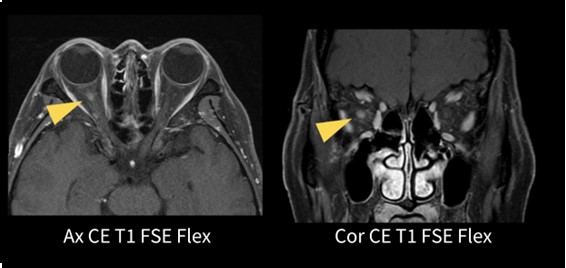

Flex (2D FSE 2point Dixon)

本症例は視神経炎の患者さんの造影検査である(図.7)。従来は3point Dixon法のIDEALのみであったが、今回2D FSEで2point Dixon法のFlexが使用可能となった。従来IDEALでは4分程度で撮像していたがFlexでは3分程度で撮像できている。眼窩内の脂肪信号の消え残りもなく、右側の視神経炎の病変部の造影効果も明瞭に観察でき良好な画像が得られている。

図7.眼窩造影(視神経炎)